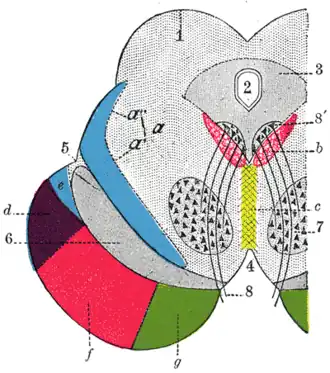

Transverse section through mid-brain.

| |